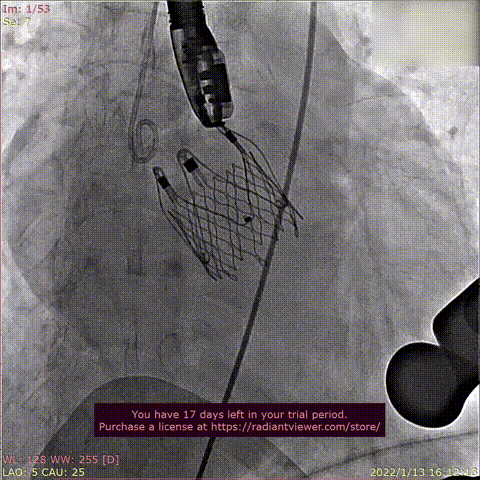

Case 5

患者为68岁男性,因“活动后心累,气紧半年,加重1周“主诉入院。术前超声提示全心增大,左室肥厚,LVDD 75mm ,LVEF 48%,主动脉瓣重度反流。术后即刻主动脉瓣大量反流消失,LVDD 59mm,左室较术前显著缩小。

瓣膜释放过程